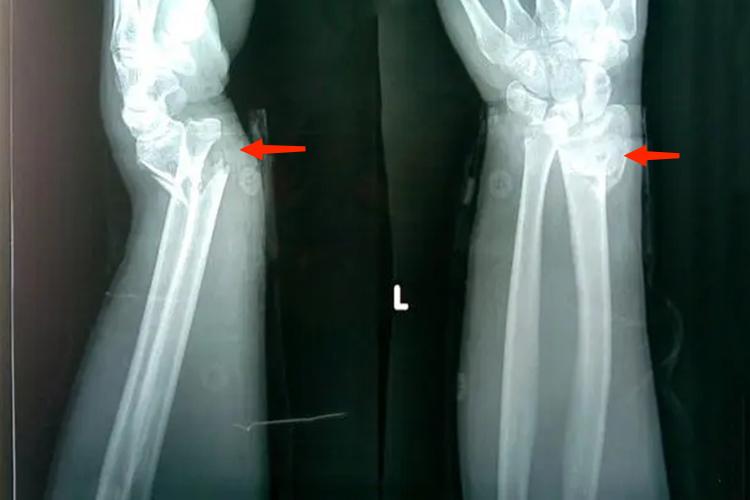

盖氏骨折又称桡骨干下1/3骨折合并尺骨小头脱位,临床表现为受伤后,前臂出现疼痛、肿胀、畸形及功能障碍。尺桡骨前后位X线片上,桡骨表现为短缩,桡骨向尺骨靠拢,尺桡骨远端骨间距离增宽。正常情况下前臂侧位X线片上,尺骨影被桡骨影遮盖,或尺骨影应不超过桡骨影背侧3mm,盖氏骨折脱位中桡骨通常向掌侧成角,尺骨头向背侧突出。